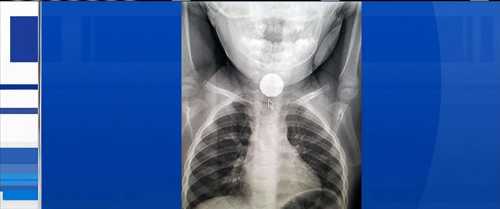

An x-ray provided the problem and solution easily, but the path to it was not so easy, and could have had tragic results had it not been for the persistence 2-year-old Katie Smith's parents:"We thought she was choking on a cracker at first, but my husband checked her airways and she was breathing fine," [Christina] Smith told ABC News today. "But she was gagging, drooling and holding her saliva,...[ Read More... ]